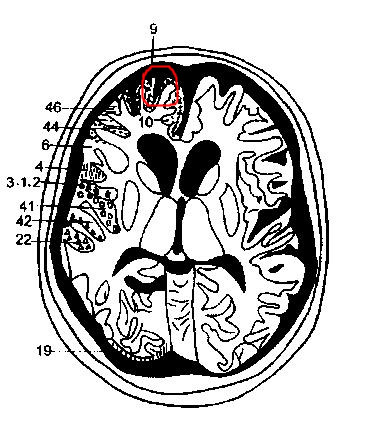

以下是引用hhcckk在2009-8-1 17:29:00的发言:[br]左侧额颞部囊状低密度影,边缘平直,有明显占位效应,考虑蛛网膜囊肿,病变导致左额颞部受压,精神症状可与此有关,李松年编的ct诊断学上有过介绍,额叶联合区损害可引起智力、性格、精神症状,也就是9、10、11区[br][br]